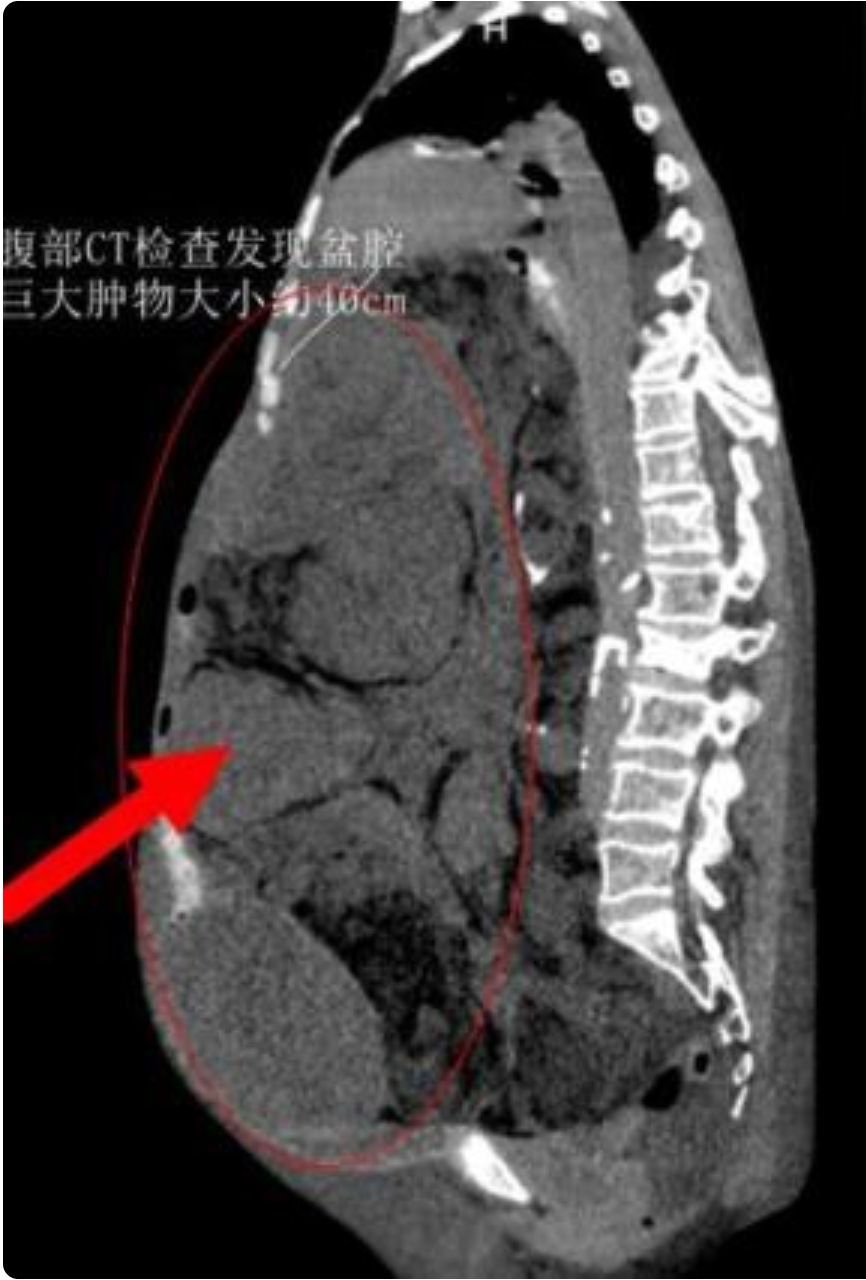

家人陪同马女士到多家医院就诊,医生均不敢贸然进行手术治疗,后辗转来到陕西省肿瘤医院诊治。通过腹部CT检查发现盆腔巨大肿物,患者无法平卧,有心脏病、肺功能下降、下肢静脉血栓、电解质紊乱、贫血等症状。

妇瘤病院二病区主任田小飞评估后认为,如此大的腹盆腔包块,在临床中比较罕见,巨大肿瘤让患者的生活质量下降,心理压力增大,甚至会产生严重并发症危及生命。受盆腔巨大肿瘤挤压,患者盆腹腔脏器已经出现移位,失去正常的解剖结构,且手术视野暴露差,肿瘤周边血管丰富,术中易造成临近脏器损伤,随时可能出现大出血、突发的呼吸、循环衰竭等,手术风险极大,手术过程极为复杂。